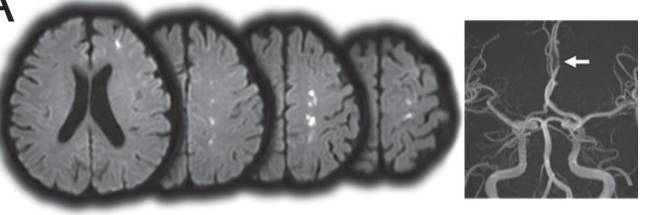

图5 DWI提示皮层多发梗死灶。MRA能够发现左侧A2-A3交界处明显狭窄。